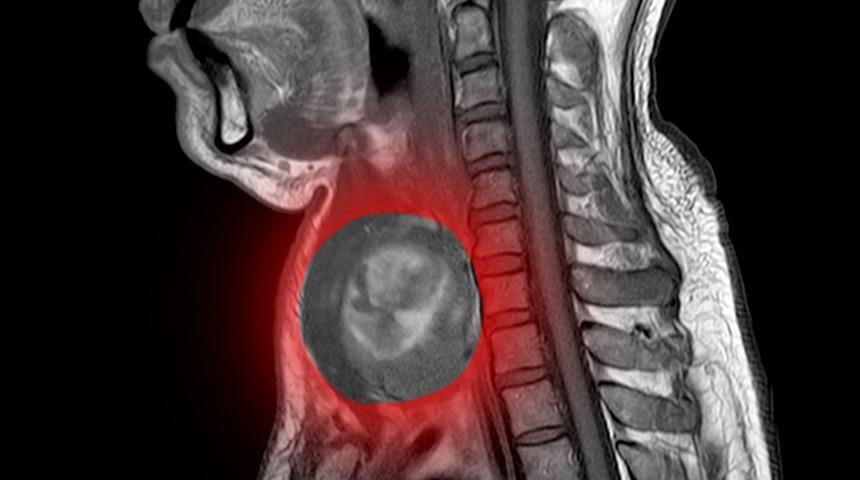

Nefes darlığı, ses kısıklığı, yutma güçlüğü gibi belirtiler veren şah damarı tümörleri çocuk yaşlarda da görülüyor. Prof. Kalko geçtiğimiz günlerde ameliyat ettikleri hastanın 5 yaşında olduğunu belirterek tıp literatüründeki en genç hasta olduğunu kaydetti.

Nefes darlığı, ses kısıklığı, yutma güçlüğü, kısmi felç gibi belirtiler veren şah damarı tümörleri genelde iyi huylu tümörlerdir. Uzmanlar bu tümörlerin mutlaka çıkarılması gereken tümörler olduğuna vurgu yaparak hastalarda ilerleyen dönemde felç geçirme veya boğularak ölme gibi tehlikelere neden olduğunu belirtiyor. Bulundukları bölge itibari ile ameliyat şansı düşük olan bu tümörler Kalp ve Damar Cerrahisi Uzmanı Prof. Dr. Yusuf Kalko’nun geliştirdiği teknikle lokal anestezi ile çıkarabiliyor. Kalko bu gibi tümörlerin genetik geçişli olduğunun altını çizerek ailede hikayesi olanların mutlaka şah damarı tümörü açısından tetkik edilmeleri gerektiğinin önemine vurgu yaptı.

Bu tarz tümörlerin genelde iyi huylu olduğunu ancak bulundukları bölge itibari ile mutlaka çıkarılmaları gerektiğini vurgulayan Prof. Dr. Yusuf Kalko,” Ender görülen bir rahatsızlık olan şah damarı tümörleri beyne giden toplardamarlara yakın bölgede olduğu için ses kısıklığı, nefes darlığı, nadir de olsa kısmi felçle sonuçlanabiliyor. Şah damarı tümörleri 3 tipten oluşuyor. Damara yapışık olmayan basit tip olarak tanımladığımız tip 1 ile damarı 180 derece saran tip 2 ve damarı 360 derece saran tip 3 dediğimiz kötü yerleşimli tümörler olarak sınıflandırılıyor. Bu tarz tümörler genellikle iyi huylu olurlar ancak bulundukları bölge itibari ile mutlaka çıkarılmaları gerekir. Çünkü burası dile, ses tellerine, nefes borusuna yakın ve hassas bir bölgedir ayrıca şah damarının ve beyne giden toplardamarların bulunduğu bölgedir. Dolayısıyla buradaki tümörler için saatli bomba tabirini kullanabiliriz.” dedi.